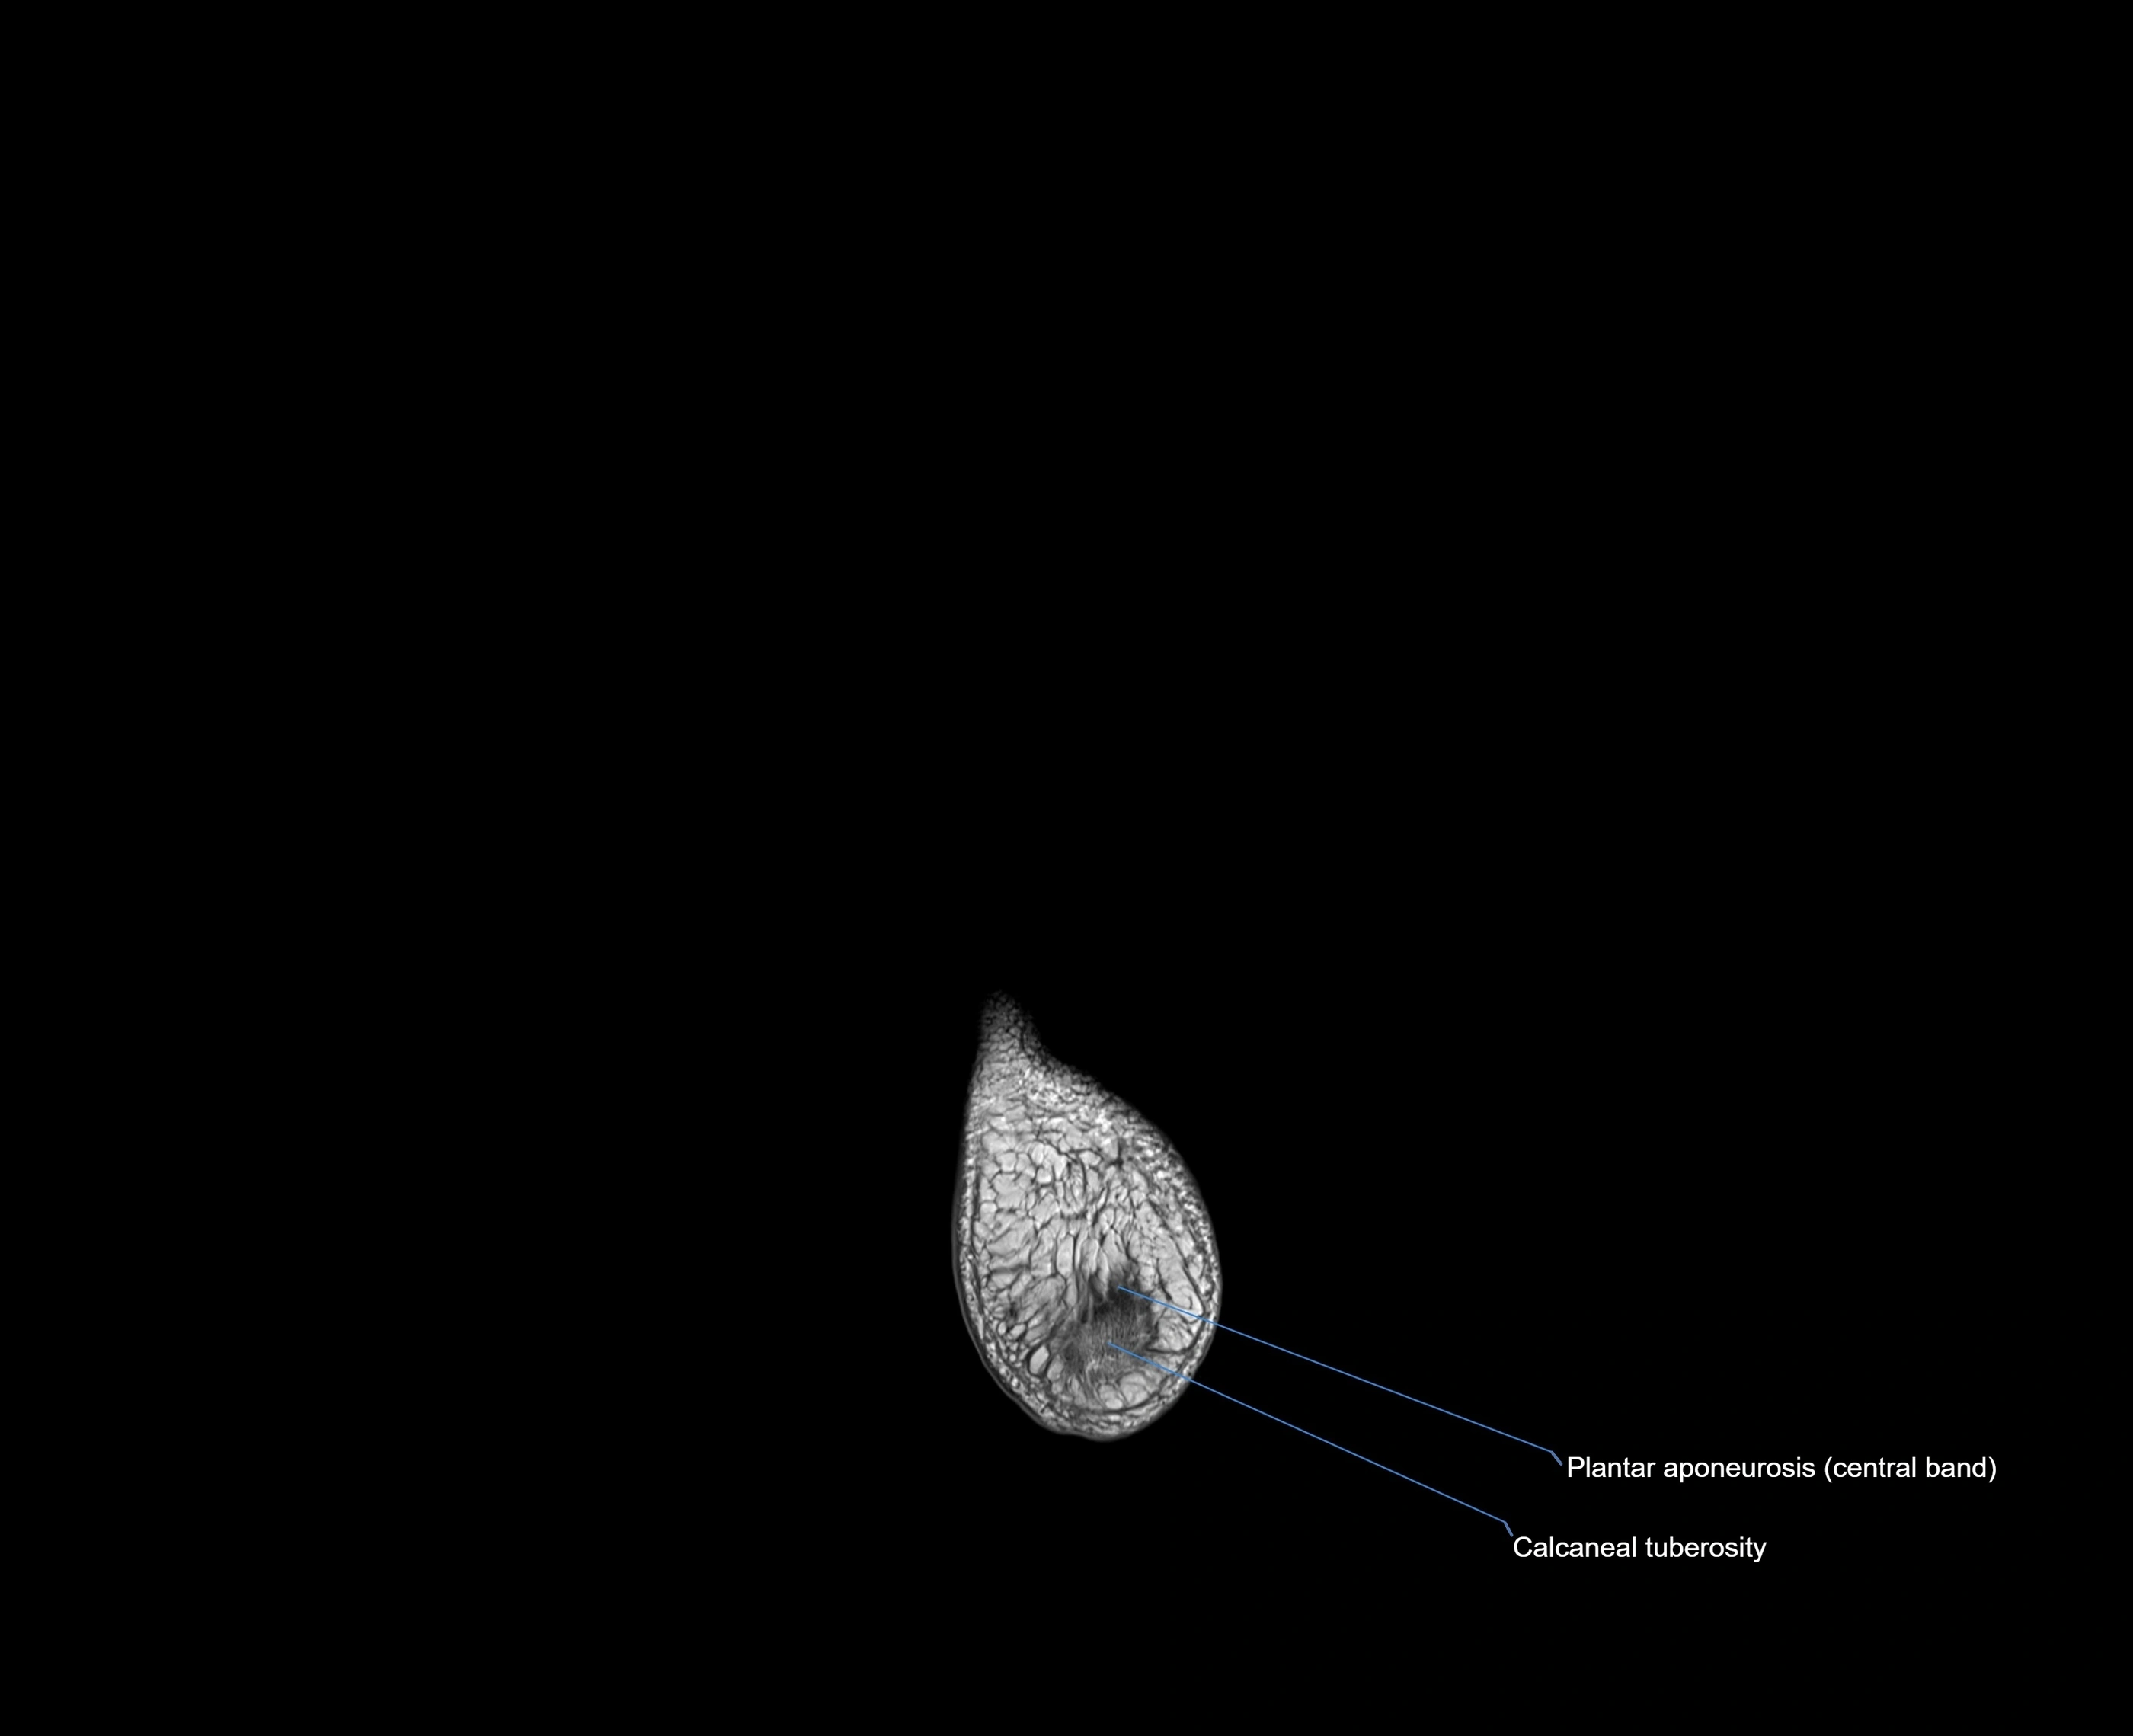

MRI image